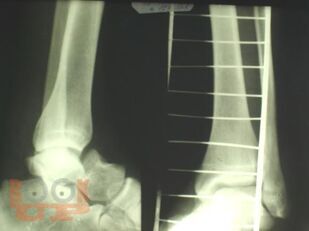

Учебно-методическое пособие содержит необходимую информацию для врачей по вопросам механизма повреждения, клиники, диагностики, осложнений и лечения переломов таранной кости. В пособии представлены биомеханические особенности дистального отдела нижней конечности. Основное внимание уделено проблеме лечения переломов таранной кости, а также осложнений переломов и переломо-вывихов таранной кости в виде развития аваскулярного некроза таранной кости. Приведены компоновки аппаратов внешней фиксации при различных типах повреждений.

В пособии обобщен более, чем 30-летний опыт лечения пациентов с переломами и переломо-вывихами таранной кости.